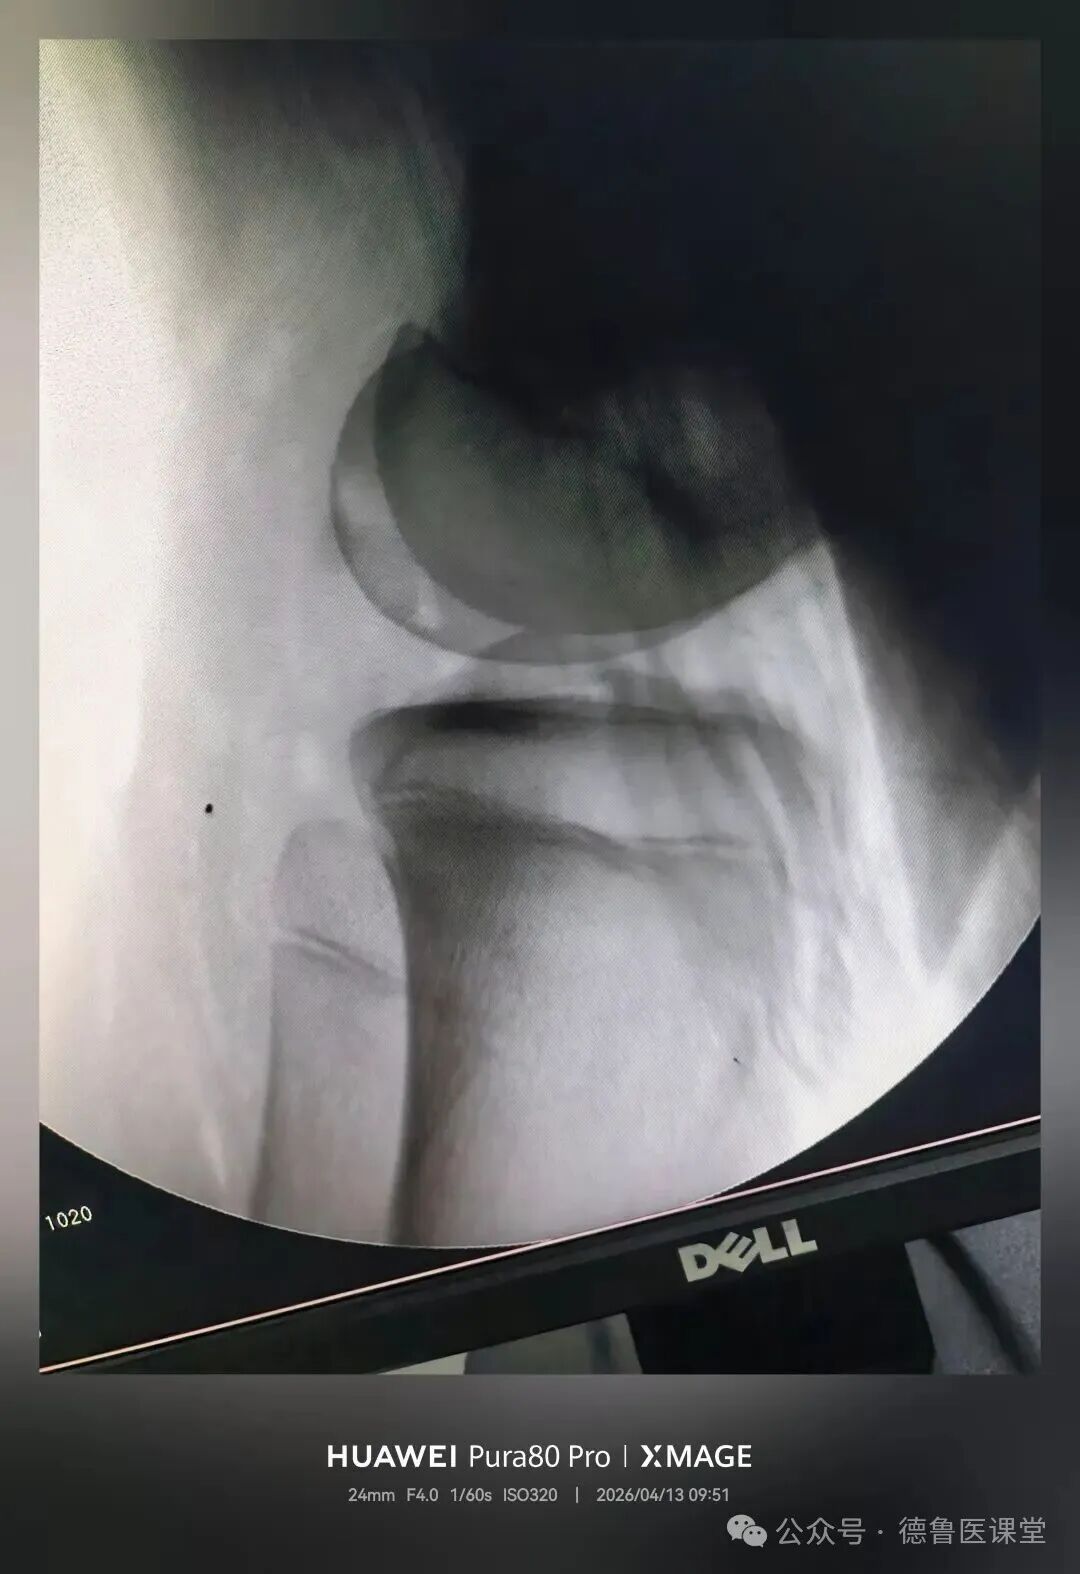

在腘横纹切

疤痕最不明显

对膝关节功能影响最小

术后直接可调式支具固定

逐步指导康复锻炼